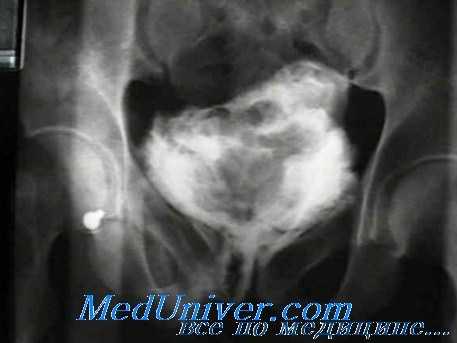

5. Каковы рентгенологические признаки повреждения мочевого пузыря?

Сдавленные боковые стенки наполненного мочевого пузыря (мочевой пузырь в виде "слезы") или мочевой пузырь, смещенный вверх (“пирог в небе”), — признаки гематомы газа, однако эти признаки не всегда говорят о перфорации стенки пузыря. При внебрюшинном повреждении мочевого пузыря затеки контрастного вещества локализуются в околопузырной клетчатке и не распространяются выше его дна. Эго обусловлено сохранением целостности брюшины.

При внутрибрюшинном разрыве пузыря затеки контрастного вещества определяются в виде отходящих от его верхушки "солнечных лучей"; затеки распространяются по боковым каналам брюшины, обтекают контур кишечника и скапливаются под печенью или селезенкой. Макрогематурия без затеков контрастного вещества характерна для ушибов мочевого пузыря.

- Рентген. Ретроградная цистография считается «золотым стандартом» диагностики этого вида травм. Разрывы органа проявляются затеками рентгеноконтрастного вещества в пузырно-прямокишечную ямку, околопузырную клетчатку, область крыльев подвздошной кости, полость брюшины.